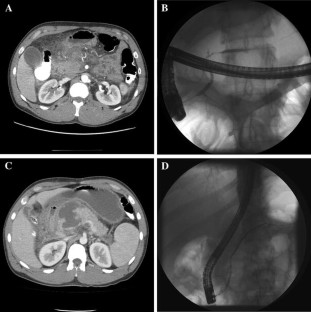

Fig. 1

Fig. 2

Fig. 3